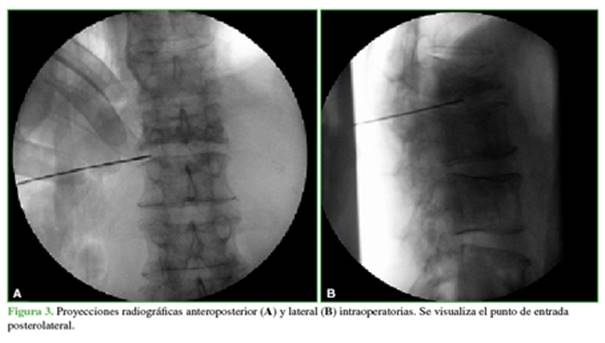

Debido a los antecedentes oncológicos, se realizó una tomografía por emisión de positrones que mostró una hipercaptación en cuerpos vertebrales de T12, L1 y L2 y en el disco intervertebral de L1-L2 (Figura 1).